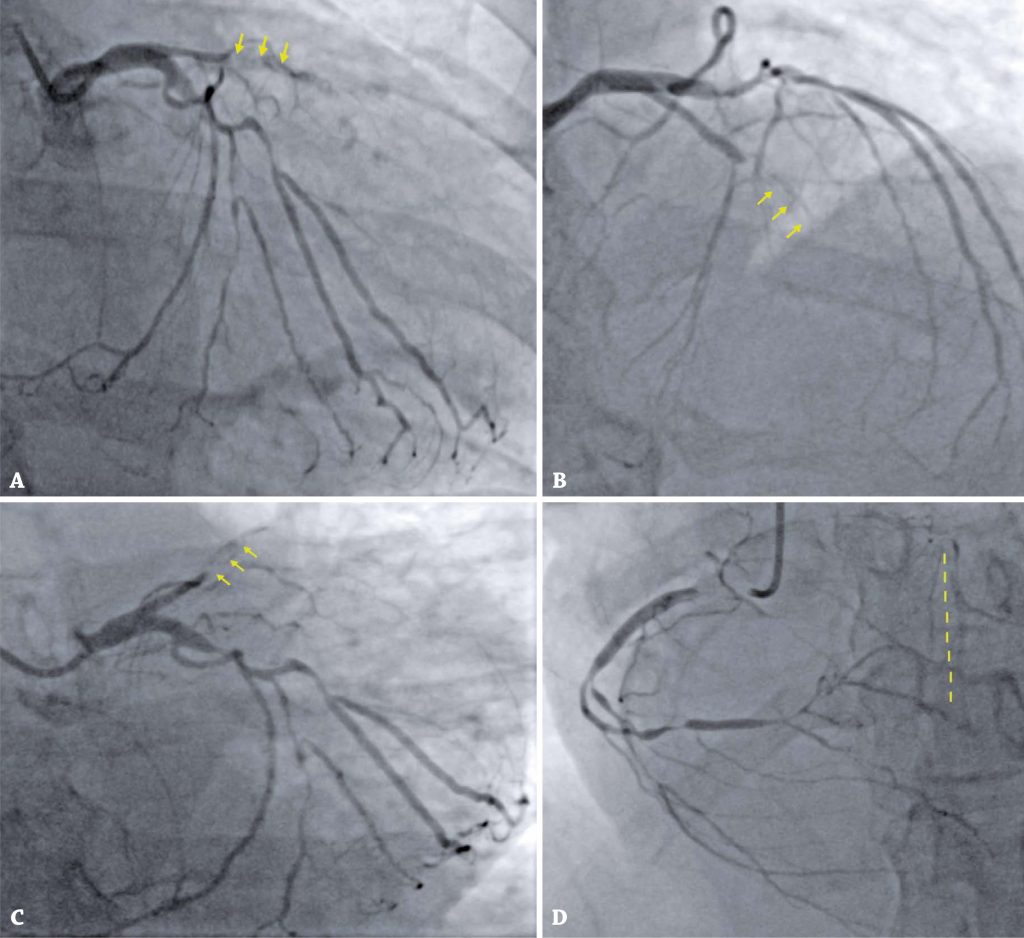

O infarto agudo do miocárdio está amplamente descrito na pandemia de COVID-19, e protocolos específicos devem ser elaborados no contexto do manejo agudo dessa condição. A relação entre injúria miocárdica e morte é bem estabelecida na literatura, estando associada a maior necessidade de ventilação invasiva e a outras complicações. O infarto agudo do miocárdio tipo 2 e a insuficiência cardíaca aguda nova são diagnosticados com maior frequência no contexto da COVID-19. Deve-se dar ênfase ao tempo ideal para procedimentos invasivos, tais como intervenção coronária percutânea e revascularização do miocárdio em pacientes positivos para SARS-CoV-2. Descrevemos o caso de uma paciente portadora de COVID-19 sem histórico de doença cardíaca prévia, admitida com sintomas de insuficiência cardíaca, apresentando marcadores de injúria miocárdica sugestivos de infarto agudo do miocárdio tipo 2.